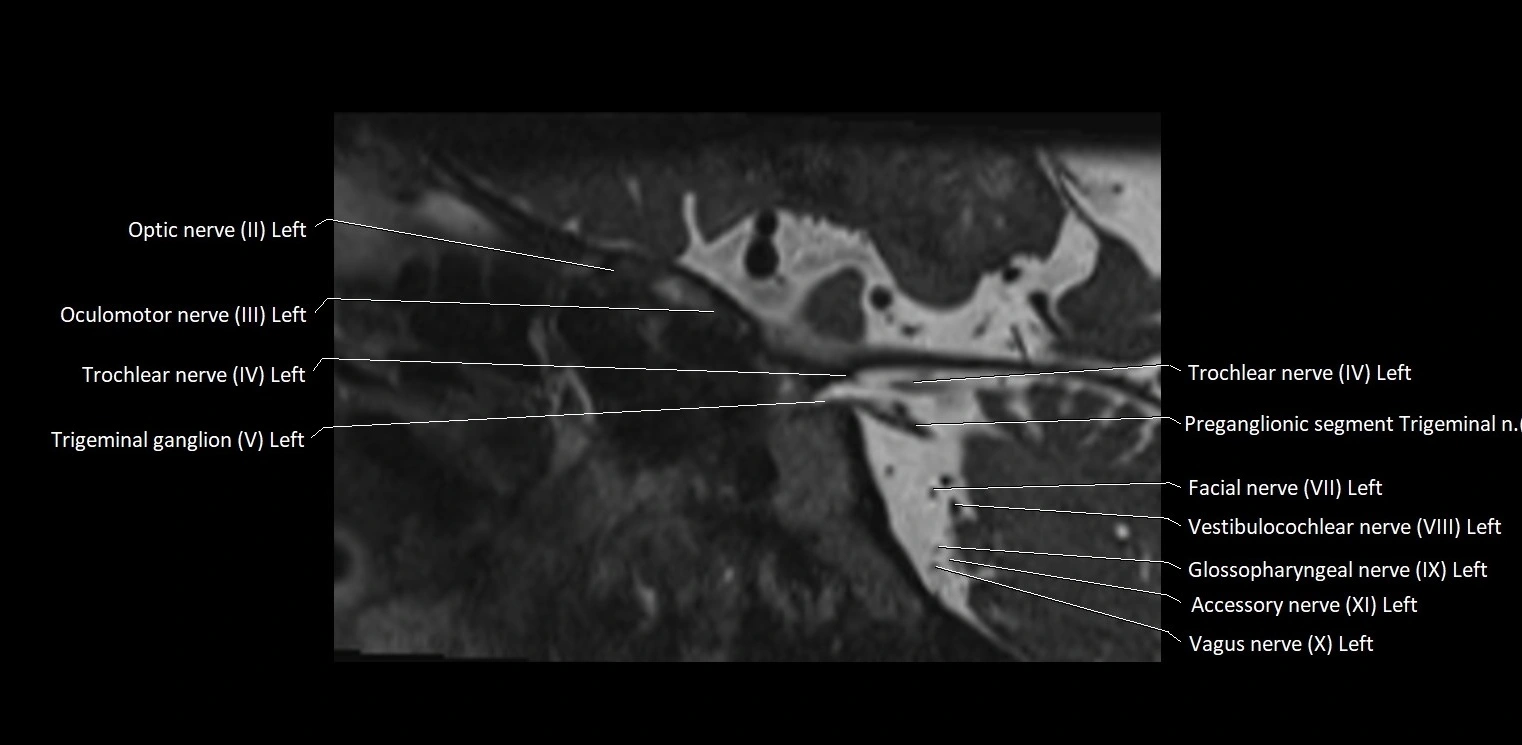

MRI Appearance

• The abducens nerve is a small, thin, linear structure

• Best visualized on high-resolution T2-weighted 3D MRI sequences (e.g., FIESTA or CISS)

• Seen as a hypointense (dark) line running from the brainstem at the pontomedullary junction, traversing the prepontine cistern, and entering Dorello’s canal under the petrosphenoidal ligament, then into the cavernous sinus, and finally the orbit

• May be challenging to visualize in standard MRI due to its small size

• Pathology may be inferred by absence, displacement, or enhancement of the nerve

MRI images

image